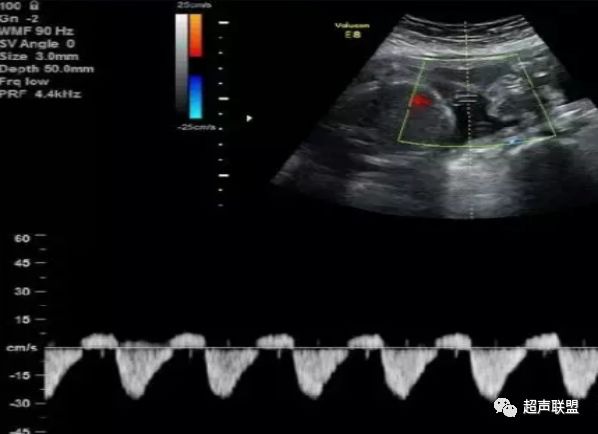

图3 正常大脑中动脉血流频谱